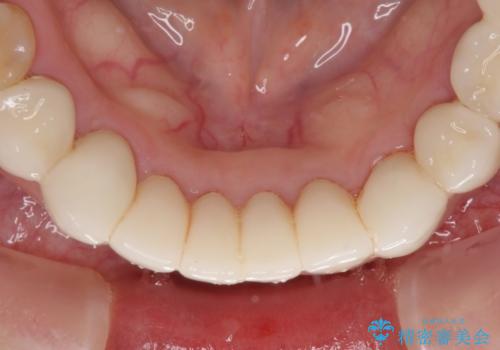

期間と費用はかかりましたが、気になっていた部分全てを改善でき、患者様には大変満足していただきました。